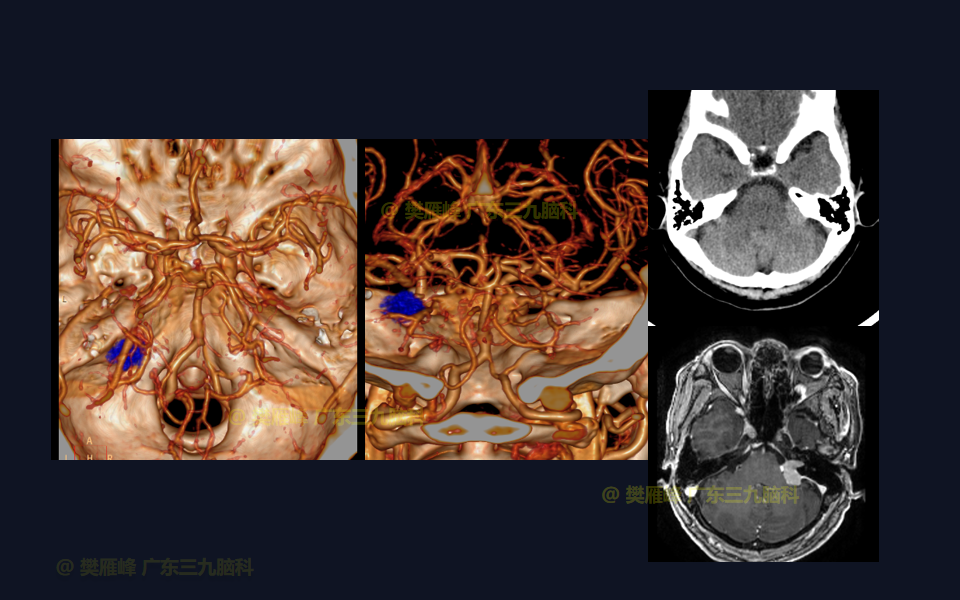

在这个二维手术视频中,展示了经枕下乙状窦后入路切除侵入内听道的桥小脑角脑膜瘤的方法。患者是一名66岁的女性,有2年左耳耳鸣伴听力下降,突发头晕半月,无面瘫病史,神经影像学显示左侧桥小脑角的侵入内听道从脑膜瘤。他接受了经乙状窦后入路保留面听神经的方法,术中肿瘤与脑干和面听神经轻度粘连,完全切除肿瘤。术后无面瘫,听力较术前明显改善,神经影像学显示肿瘤完全切除。我们展示了安全的颅神经和肿瘤切除术的细微差别和技术要点。

在这段手术视频中,展示了一名66岁女性的病例,他因左耳耳鸣伴听力下降2年余,突发头晕半月发现的左侧桥小脑角区脑膜瘤